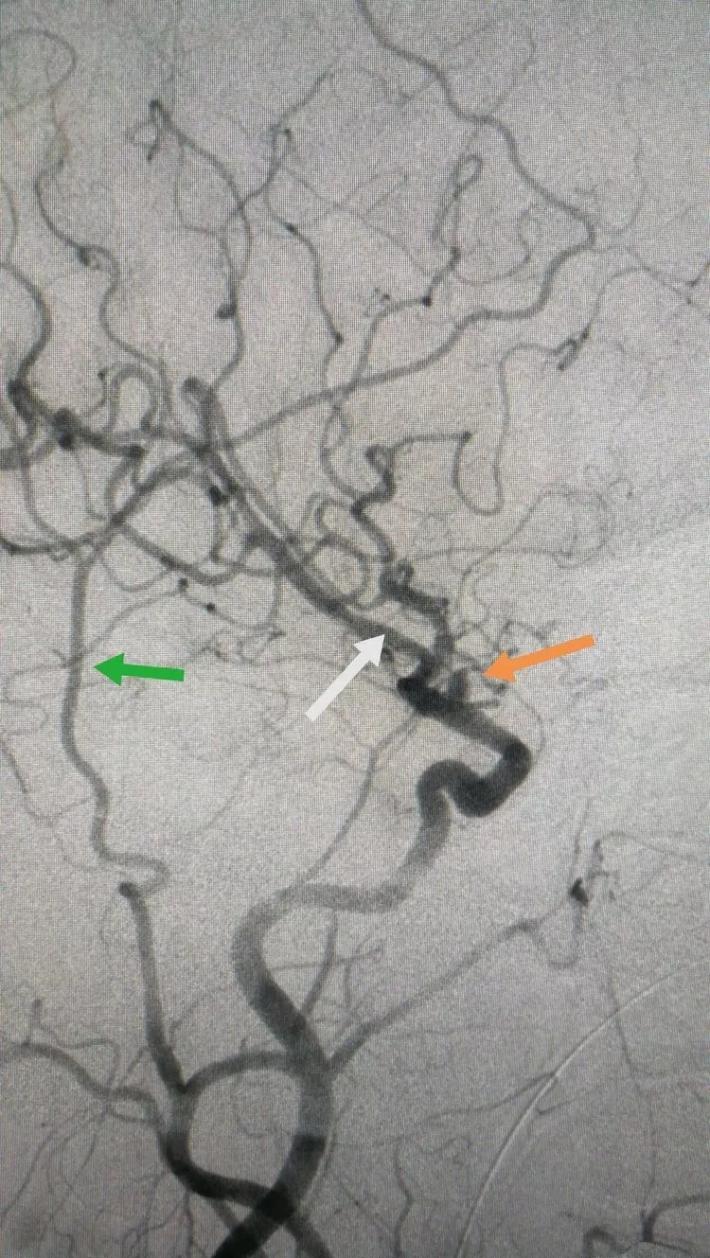

二次复合手术中DsA,黄箭→BBA,白箭→M1,绿箭→STA,M1由于痉挛与STA管径相当,病人有部分开放的前交通,所以本例我们采取的策略是①单支STA一M2搭桥②ICA颅外段阻断③BBA包裏夹闭or孤立④如包裏夹闭失败行孤立术则行STA一M2双支搭桥。